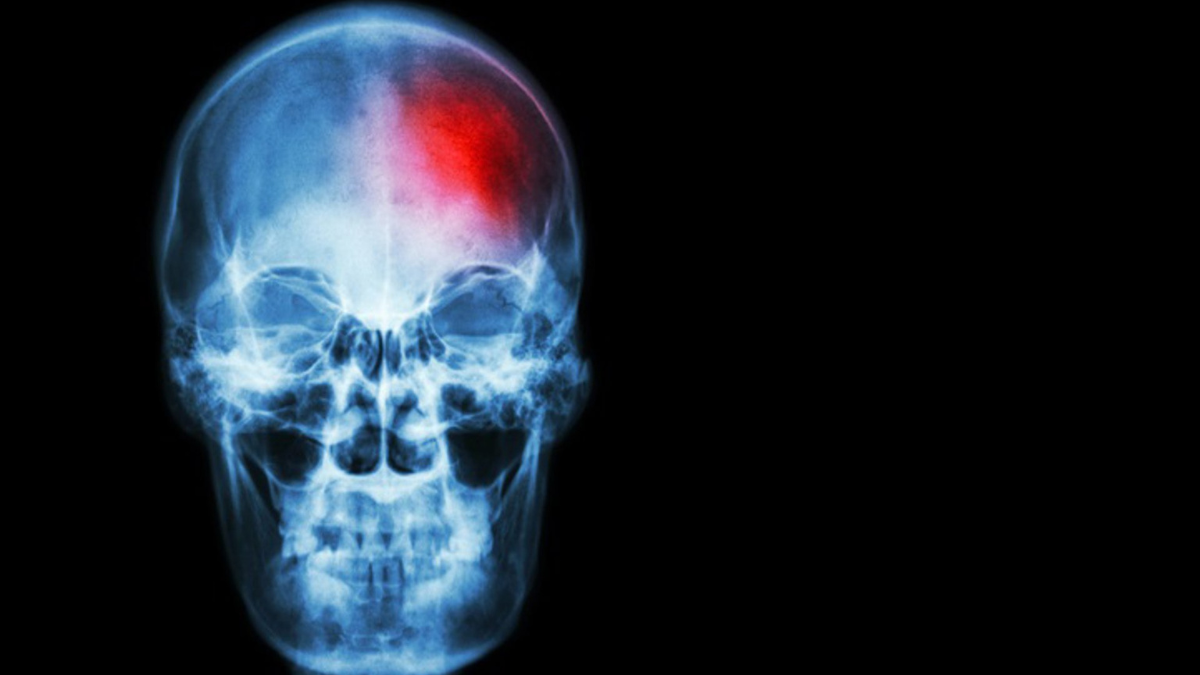

Ictus. | EP

La doctora Mª Mar Freijo, coordinadora del Grupo de Estudio de Enfermedades Cerebrovasculares de la SEN, explica que “el ictus es una enfermedad cerebrovascular que se produce cuando el flujo de sangre al cerebro se interrumpe o se reduce”. Existen dos tipos principales: el ictus isquémico, que representa el 80% de los casos, y el hemorrágico, que supone el 20% restante. En ambos, la rapidez de actuación es esencial: “Por cada minuto que pasa sin que la sangre llegue al cerebro, se pierden casi dos millones de neuronas”, advierte la especialista.